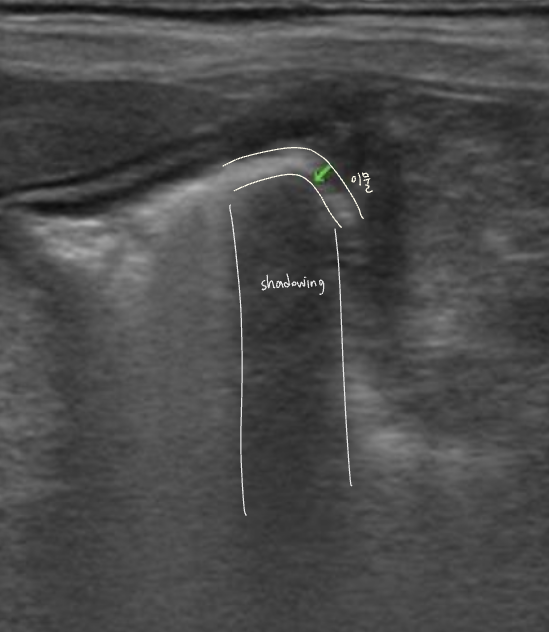

์ด๋ฌผ์ ์ด์ํ์์์ shadowing ๋ฐ์, ์์ฆ์ X-ray๋ณด๋ค ์ด์ํ๊ฐ ์ฐ์ ๋๊ธฐ๋ ํจ.

- ์์ ๊ธ์ฌ โ ์ ์์ธ์์ ์ด์ํ ๊ฒ์ฌ โ shadowing์ ๋ณด์ด๋ ์ด๋ฌผ์ ์ฆ๊ฑฐ ํ์ธ